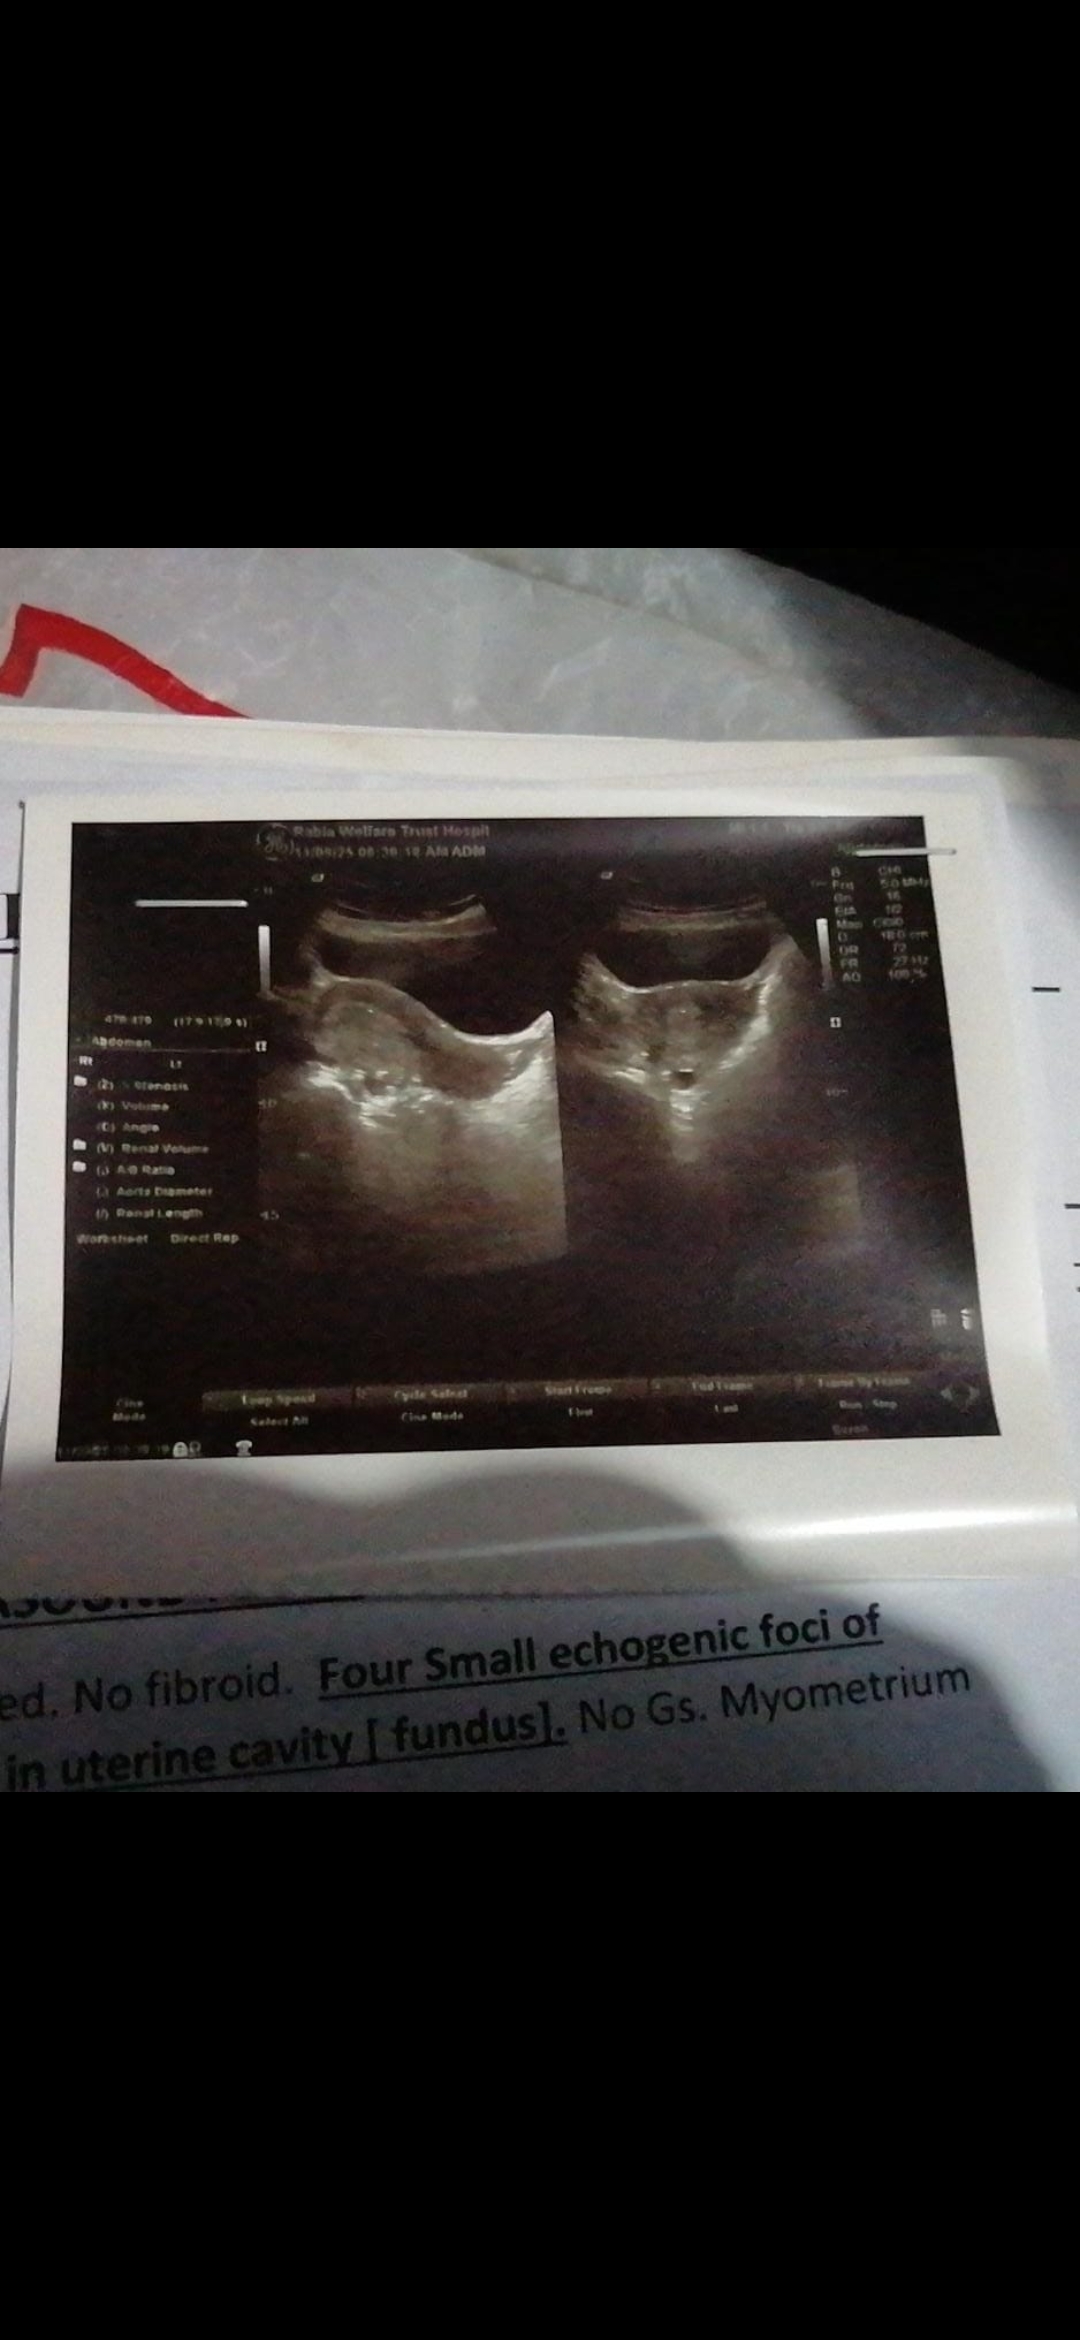

I have miscarriage and dr gave me medicine to remove all the pieces from the uterus i did ultrasound first they said its normal theres no procs but i dont have period for 3 month and juat 2 time in 3 three month spotting and now when i go to dr she did ultrasound and said there's 4 pieces inside 1mm

Attach Photo here: